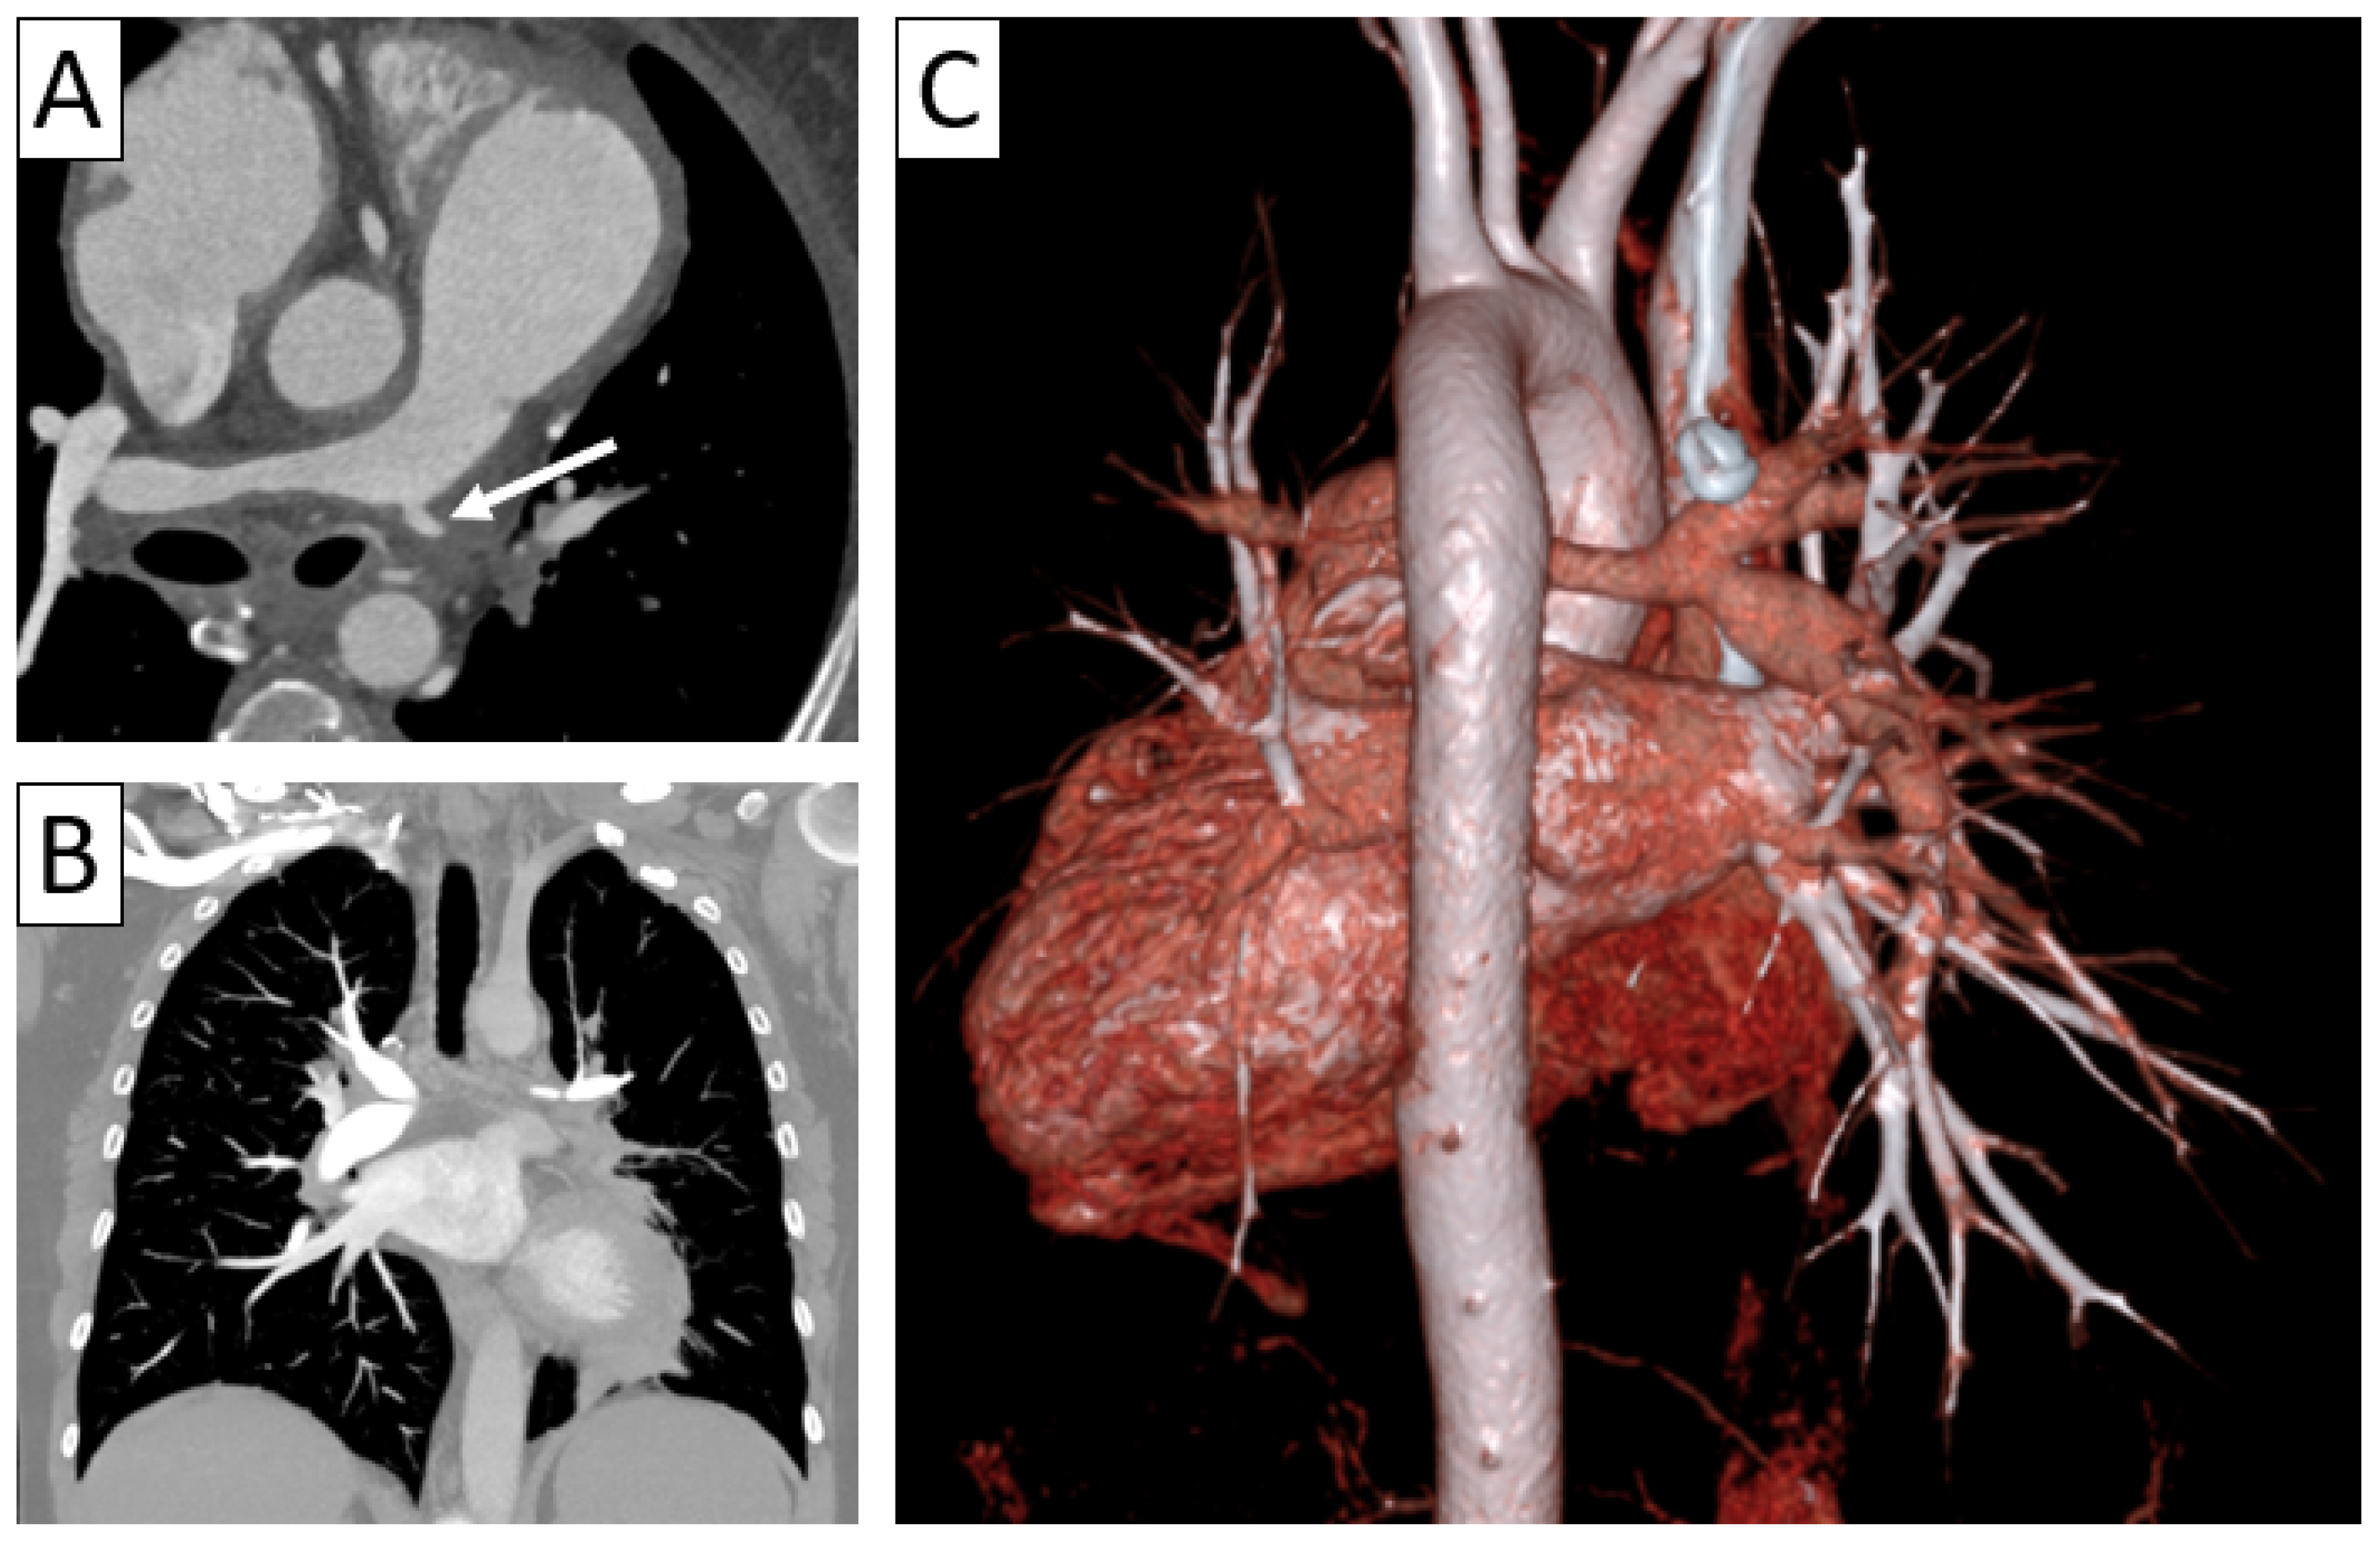

| CTA | Circumferential parietal thickening Vessel wall enhancement | Circumferential parietal thickening Vessel wall enhancement Luminal stenosis or narrowing |